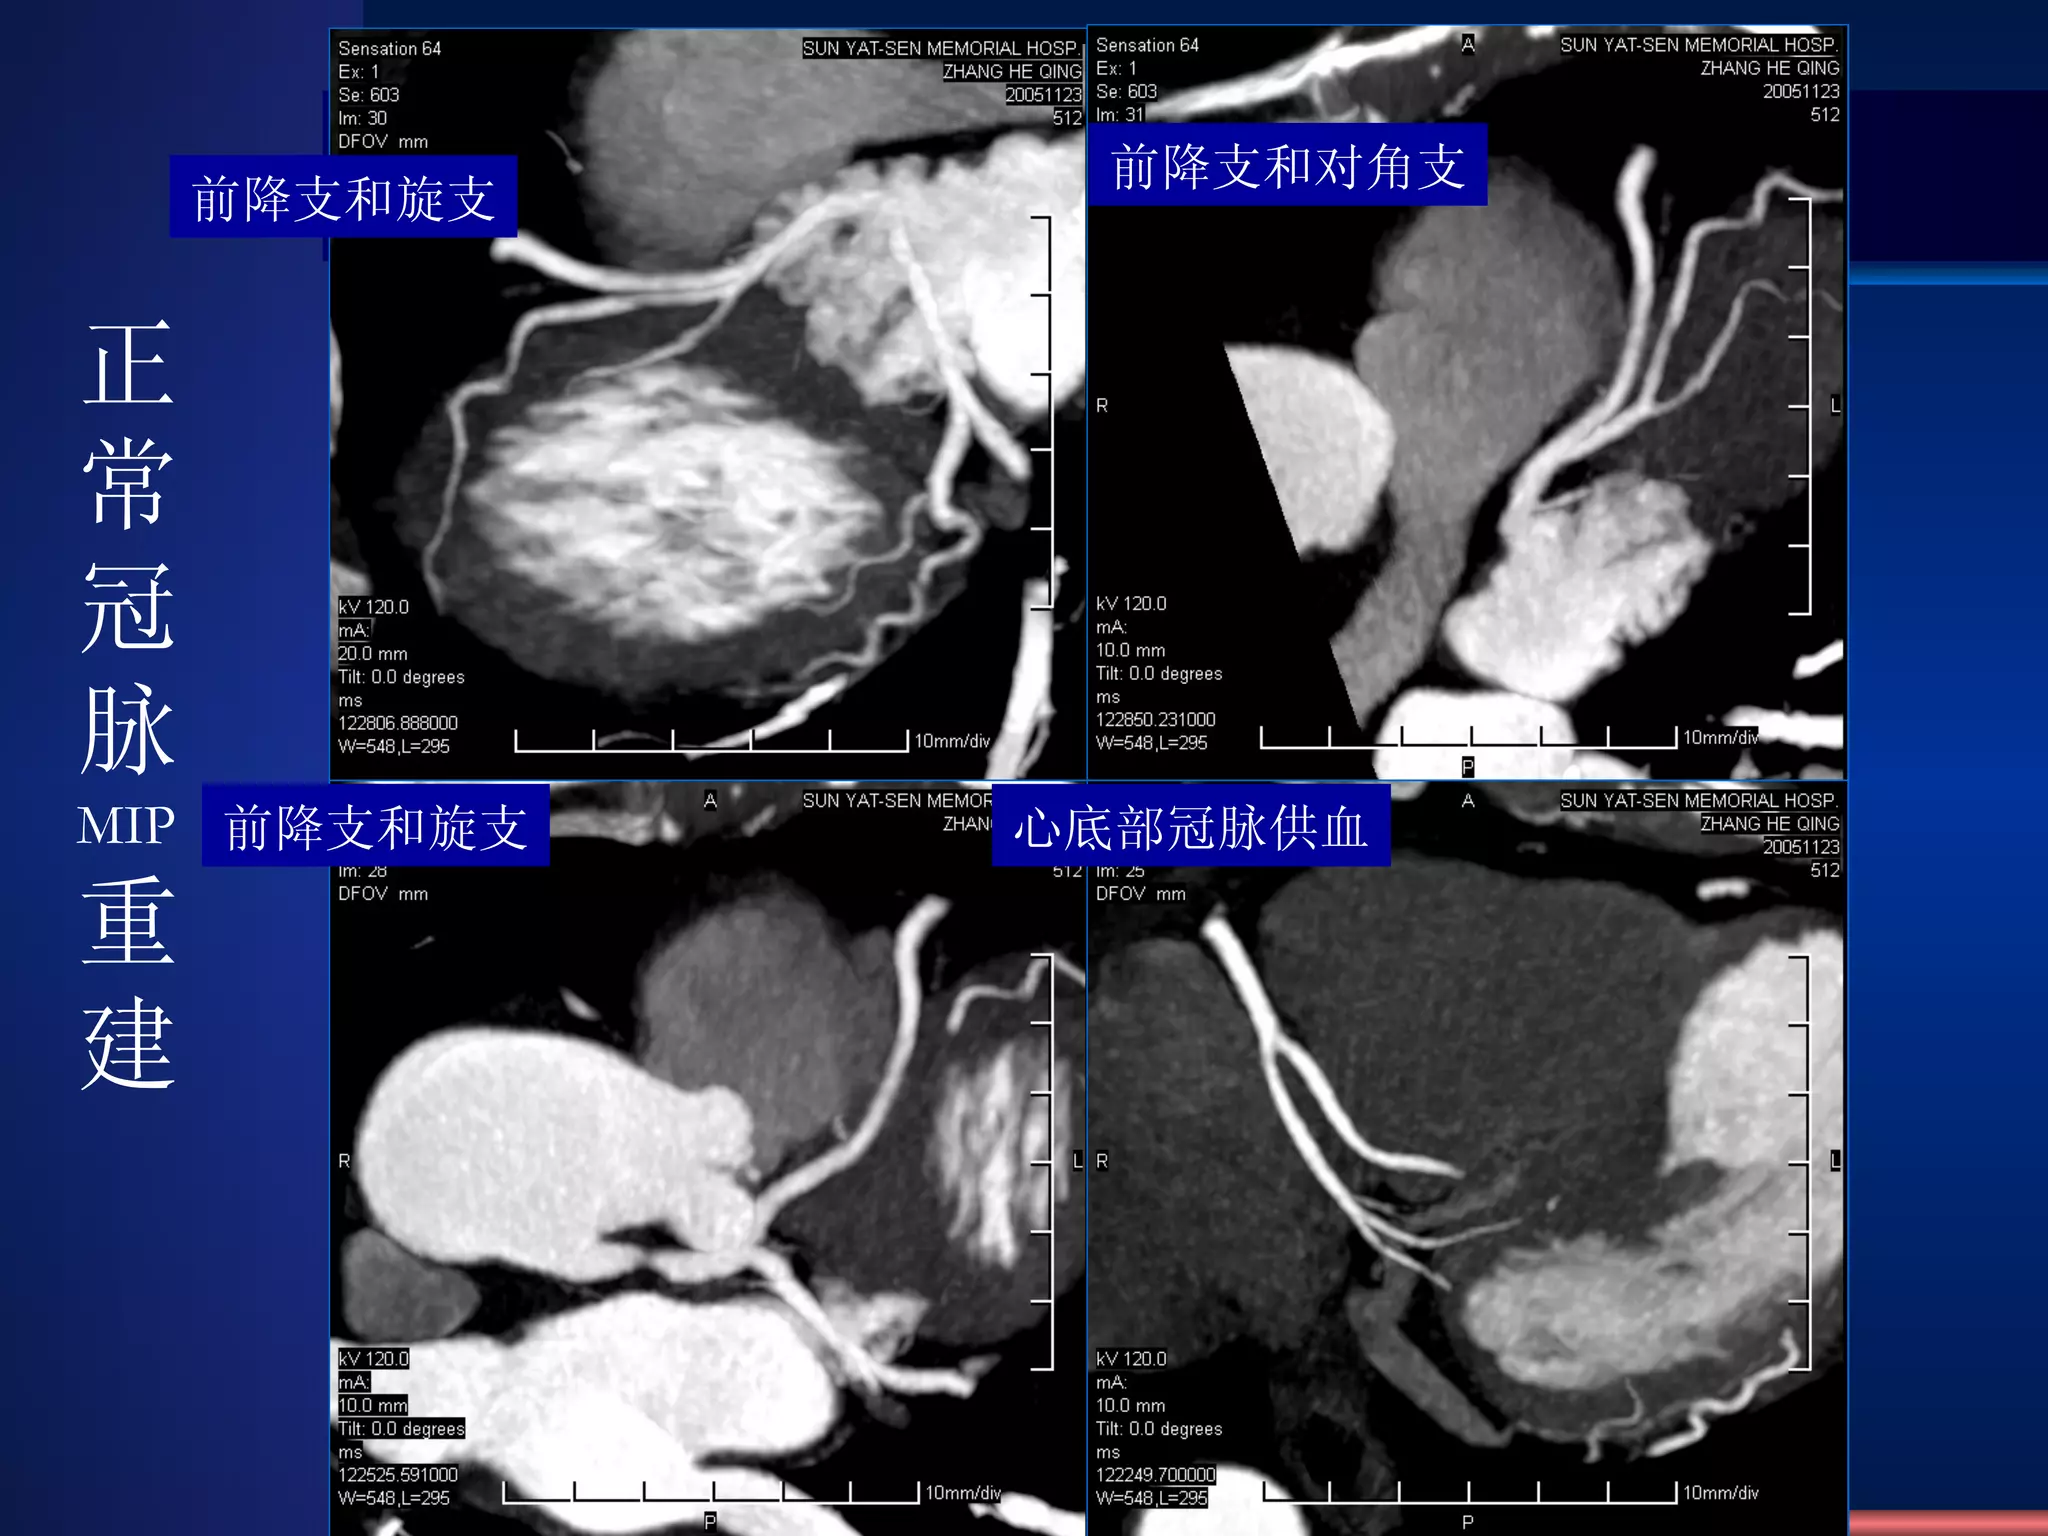

Coronary artery CTA MIP With Contrast Medium

VRT Recon. Normal Coronary artery CTA

前降支和旋支 前降支和对角支 前降支和旋支 心底部冠脉供血 正常冠脉 MIP 重建

Coronary artery CTAMIP With Contrast Medium

VRT Recon. NormalCoronary artery CTA

前降支和旋支 前降支和对角支 前降支和旋支心底部冠脉供血 正常冠脉 MIP 重建